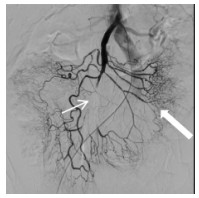

消毒右侧腹股沟区,经右侧股动脉入路。经穿刺点置入5F血管鞘,0.035 -in导丝引导5F Cobra导管进入SMA近端,造影(造影剂速度4~6 mL/s,时间3~4 s),明确病变位置及肠系膜远端血供情况。造影可见SMA近端呈夹层样改变(图 2细箭头示),空肠动脉分支近端呈假性动脉瘤样改变(图 2粗箭头示),虽然有夹层出现,但SMA主干全程尚通畅。更换8F血管鞘,应用导管导丝技术送入肝素涂层血管内覆膜支架(7 mm×25 mm)覆盖于夹层段并造影,发现病变段未完全封闭(图 3细箭头示)。主要由于为尽量减少支架对远端正常分支血管的影响,第一枚支架长度略短,因此再植入一枚支架(8 mm×25 mm)与第一枚叠加。再次经SMA造影,发现SMA主干内对比剂滞留(图 4),SMA中主干远端及其分支血管未显影。同时患者出现腹痛加重、气促、心率减慢至约40~50次/min,血压高压达到180/100 mmHg,考虑患者发生急性动脉血栓形成。紧急予面罩吸氧,静脉注射阿托品肌0.5 mg。经导管于SMA应用尿激酶25万U、肝素3 000 U进行持续灌注,灌注时间约5~8 min。应用球囊(8 mm×50 mm)扩张支架。最后再次经SMA造影,可见SMA主干近端再通,夹层瓣膜及其附近病变空回肠血管未再显影。病变远端空回肠动脉分支大部分恢复通畅(图 5粗箭头示),但SMA主干远端部分血管仍有部分未溶解血栓(图 5细箭头示),术后回病房每天皮下注射低分子肝素钙2 500单位,2次/d;患者腹痛症状当即减轻,生命体征恢复正常。

| 图 5 紧急经导管注入肝素、尿激酶后,大部分分支血管恢复开通(粗箭头示) |